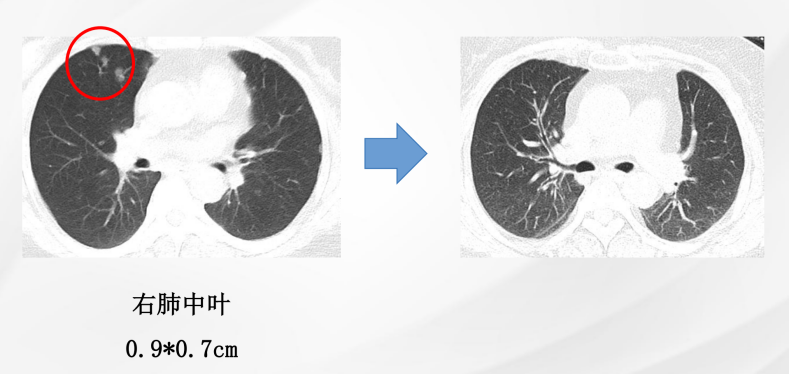

患者为女性,60岁,已绝经,既往史无特殊。2021年5月10日于院内行乳腺及淋巴结彩超检查,提示右乳腺实性结节(BI-RADS 4C级)及右腋下肿大淋巴结。进一步影像学评估显示,右乳原发灶大小约2.7×2.3 cm,右腋窝淋巴结约1.8×1.3 cm;同时可见双肺结节,最大约0.9×0.7 cm,并见右肺门淋巴结约1.1×1.0 cm。整体影像学结果提示患者初诊时已存在乳腺原发灶伴区域淋巴结及肺部转移。

图3:双肺结节

治疗2个月后影像学复查结果示:右乳腺原发灶由2.7 × 2.3 cm缩小至2.4 × 2.1 cm;右腋窝淋巴结由1.8 × 1.3 cm缩小至1.3 × 0.9 cm;右肺中叶结节由0.9 × 0.7 cm缩小至0.7 × 0.6 cm;右肺门淋巴结由1.1 × 1.0 cm缩小至1.0 × 0.9 cm。本次复查显示乳腺原发灶缩小11%腋窝淋巴结、肺病灶、右肺门淋巴结均缩小。总体疗效评估为疾病稳定(SD)。这提示患者在治疗早期即出现客观影像学改善,但尚未达到部分缓解(PR)阈值。

治疗12个月后,患者疗效进一步加深。右乳腺原发灶缩小至1.2 × 0.9 cm;右腋窝淋巴结缩小至0.5 × 0.3 cm;右肺中叶原结节影未再显示;右肺门淋巴结缩小至1.0 × 0.4 cm。本次复查显示乳腺原发灶缩小56%;同时腋窝淋巴结、肺病灶及右肺门淋巴结均达到影像学CR,整体疗效由早期SD进一步转化为PR。对晚期HR+/HER2-乳腺癌而言,这种由初期肿瘤控制向持续缓解的演变,具有较强的临床意义。

截至治疗4年6个月时,患者仍维持持续获益。右乳腺原发灶缩小至0.6 × 0.5 cm;右腋窝淋巴结缩小至0.4 × 0.3 cm;右肺中叶原结节影未再显示;右肺门淋巴结缩小至0.7 × 0.4 cm。本次复查显示乳腺原发灶缩小78%;腋窝淋巴结、肺病灶、右肺门淋巴结影像学CR。总体疗效评估为持续PR。